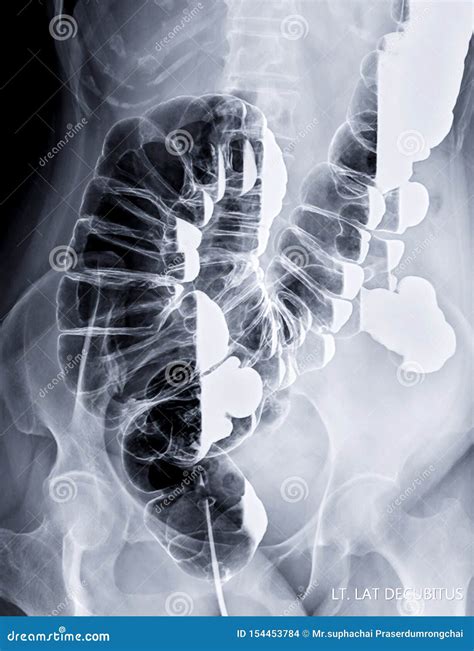

• Colonoscopies: This position is often used during colonoscopies to provide better access to the colon and rectum.

• Diagnostic Imaging: This positioning is also used in diagnostic imaging procedures such as CT scans and MRIs to provide better visualization of the targeted area.

2. Position the Patient: Help the patient lie on their left side. Ensure the body is aligned in a straight line from head to toe.